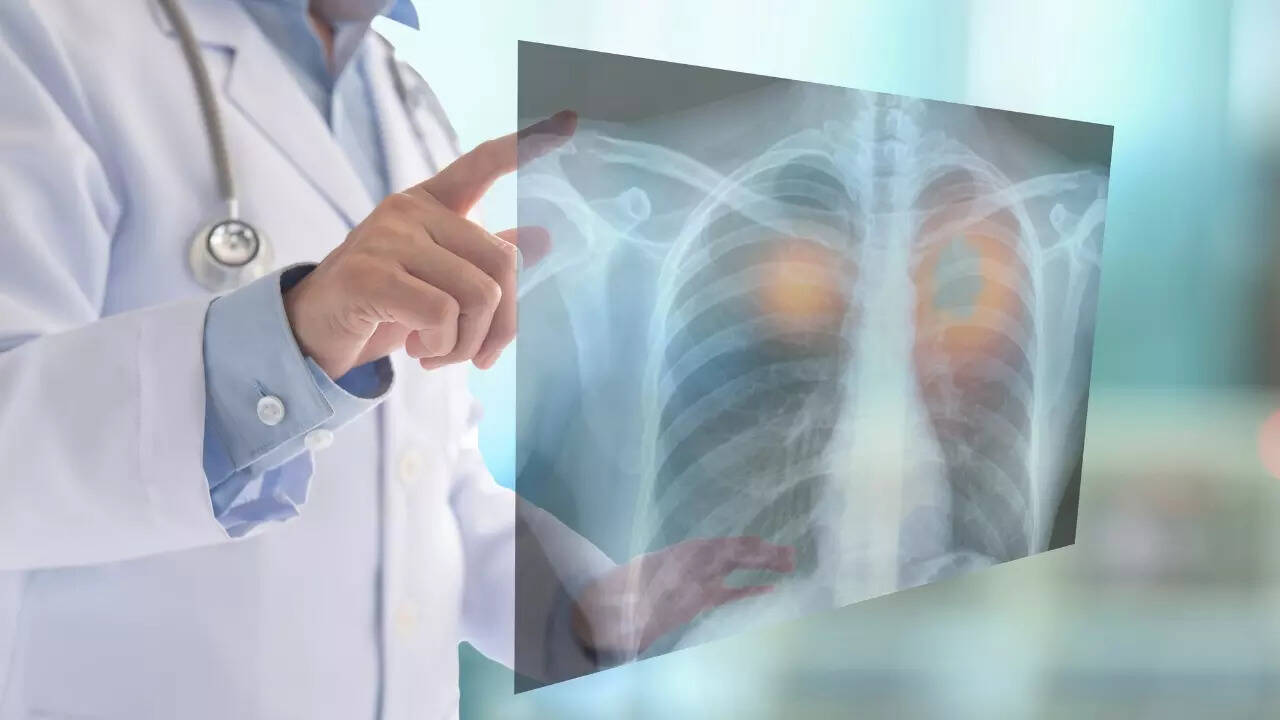

World Lung Cancer Day 2023: फेफड़ों का कैंसर एक प्रकार का कैंसर है जो फेफड़ों में शुरू होता है। यह दुनिया भर में कैंसर से संबंधित मौतों का प्रमुख कारण है। फेफड़ों के कैंसर के दो मुख्य प्रकार हैं। पहला है नॉन-स्मॉल सेल लंग कैंसर (एनएससीएलसी) और दूसरा है स्मॉल सेल लंग कैंसर (एससीएलसी)। फेफड़ों का कैंसर लंग के टिश्यू में पैदा होता है। यह आमतौर पर उन सेल्स में फैलता है जो एयरवेज को रेखांकित करती हैं और शरीर में लिम्फ नोड्स या अन्य अंगों में भी फैल सकती हैं।

यह पुरुषों और महिलाओं दोनों में कैंसर से होने वाली मृत्यु का एक प्रमुख कारण है। नॉन-स्माल सेल लंग कैंसर (NSCLC) और स्माल सेल्स लंग कैंसर, फेफड़ों के कैंसर (SCLC) के दो मुख्य उपप्रकार हैं। सबसे आम प्रकार, NSCLC, SCLC की तुलना में अधिक धीरे-धीरे बढ़ता और फैलता है।